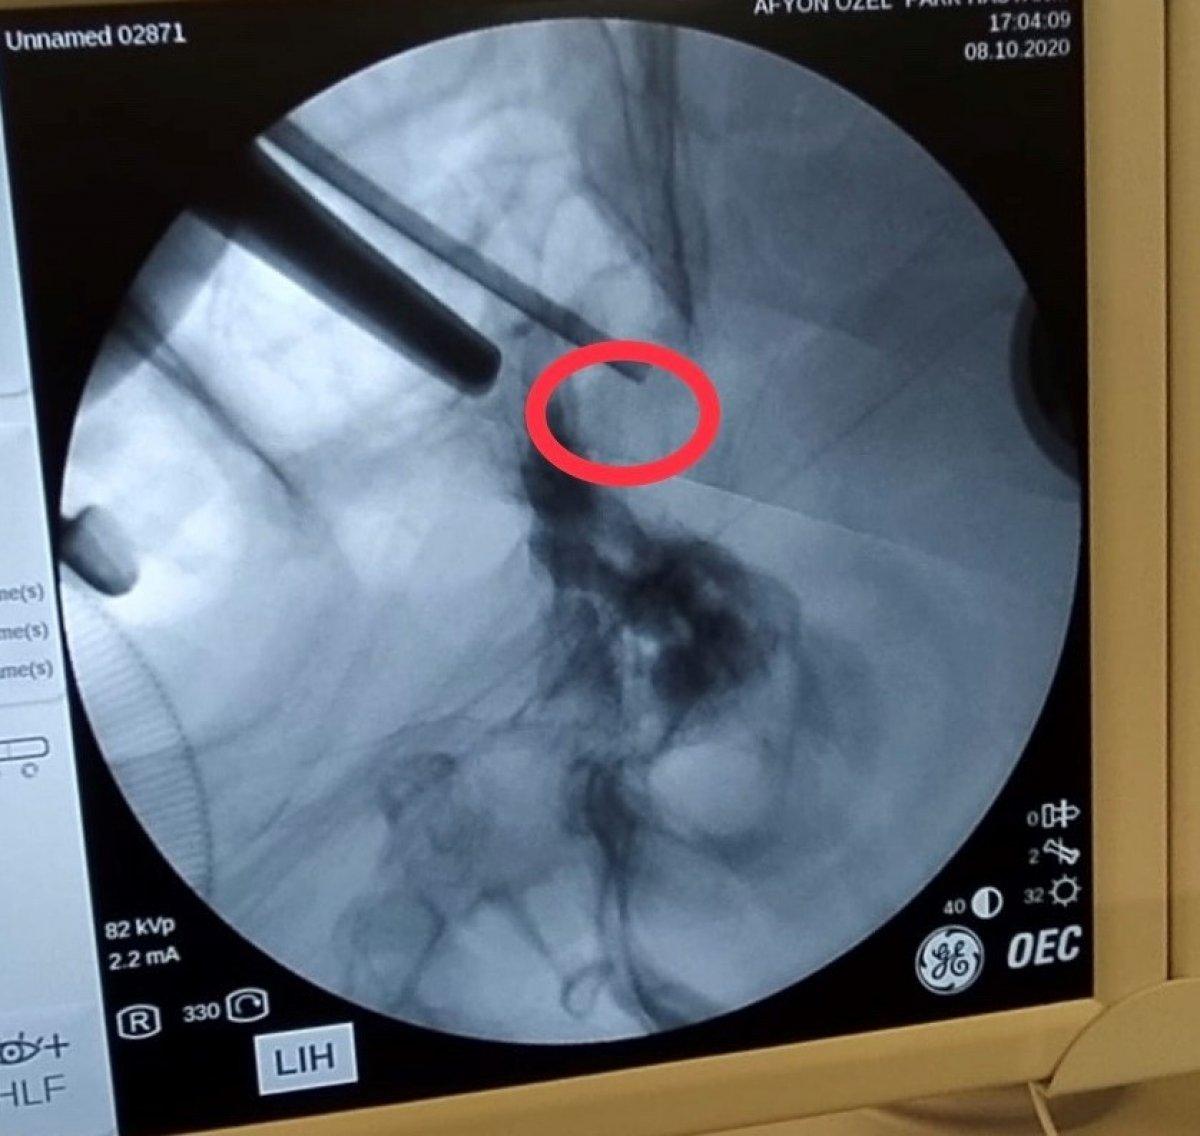

Ameliyata alınan hastanın burun deliklerinden girilerek beynindeki tümör alındı.

Operasyon sonrası açıklamalarda bulunan Çakır, transsfenoidal cerrahinin burun boşluğundan girilip hipofiz tabanına ve oradan hipofize ulaşılıp yapılan cerrahi olduğunu söyledi.

Çakır, "Hastamız da 72 yaşında, ani gelişen göz kapağında düşme, görme kaybı ve şiddetli baş ağrısı ile bize geldi. Hastanın tetkiklerinde sella dediğimiz kafa tabanında hipofiz bezinin yerleştiği boşlukta büyük bir kitle ve buna bağlı bu bölgedeki kranial sinirlerin bası altında kaldığını görerek cerrahi kararı aldık. Hastaya transsfenoidal girişimle tümörü tamamen boşalttık ve problemsiz olarak servise aldık" dedi.